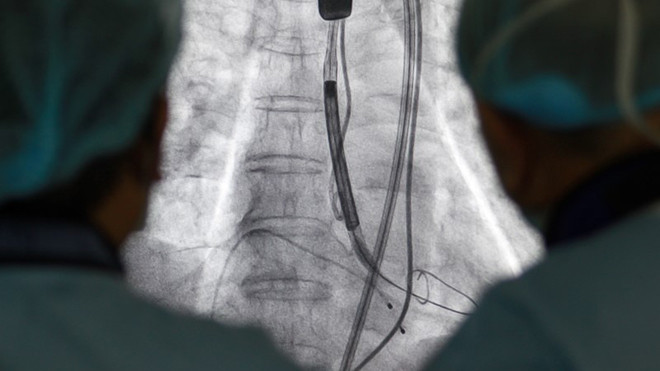

Ống thông được luồn qua da từ động mạch đùi đến động mạch chủ để thay van tim cho bệnh nhân

Giải pháp tối ưu với ông Chính là thay van động mạch chủ qua da (TAVI). Đây là một trong những kỹ thuật thay van tim hiện đại và phức tạp nhất thế giới. Với kỹ thuật này, các bác sỹ sẽ luồn ống thông qua da từ động mạch đùi đến động mạch chủ để thay van tim, giúp tăng khả năng thành công, giảm nguy cơ chảy máu, tránh được nhiều biến chứng nguy hiểm. Thời gian phục hồi của người bệnh cũng nhanh hơn - chỉ từ 2 đến 6 ngày so với 1 - 2 tuần nếu mổ mở.